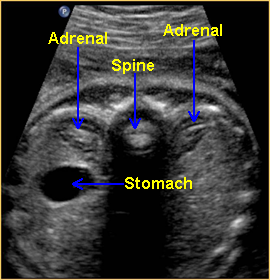

Normal Adrenal Gland

Above. Transverse view. The normal adrenal glands appear as crescent shaped structures superior to the kidneys. When well visualized, the more echogenic gland may be surrounded by mixed or reduced echos.

Above. Partial coronal view. Again, normal adrenal gland demonstrating crescent shape.